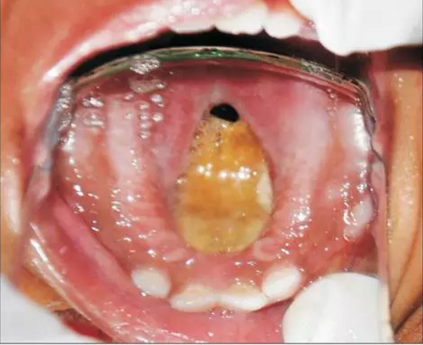

患者為18個(gè)月齡的幼兒,主訴為口腔上腭大面積潰瘍伴鼻腔反流及口腔異味?;純?個(gè)月前曾在外院治療過肺炎,治療過后一個(gè)月,患兒家長發(fā)現(xiàn)患兒上腭出現(xiàn)一小潰瘍并再一次就診。潰瘍在三天內(nèi)顯著增大并導(dǎo)致上腭穿孔?;純撼霈F(xiàn)吞咽困難及鼻腔反流等癥狀。為求治療穿孔及相關(guān)癥狀及預(yù)防吸入性肺炎來我院就診。患兒沒有糖尿病、惡性血液病等病史,也沒有鼻竇炎或流涕等癥狀。口內(nèi)檢查發(fā)現(xiàn)上腭一暴露骨面的巨大潰瘍,范圍從腭中縫至軟腭,局部穿孔。患兒口底、舌、頰粘膜、唇、鼻中隔皆正常,上頜乳切牙、乳側(cè)切牙、左下頜第一乳磨牙已萌出。

1.png